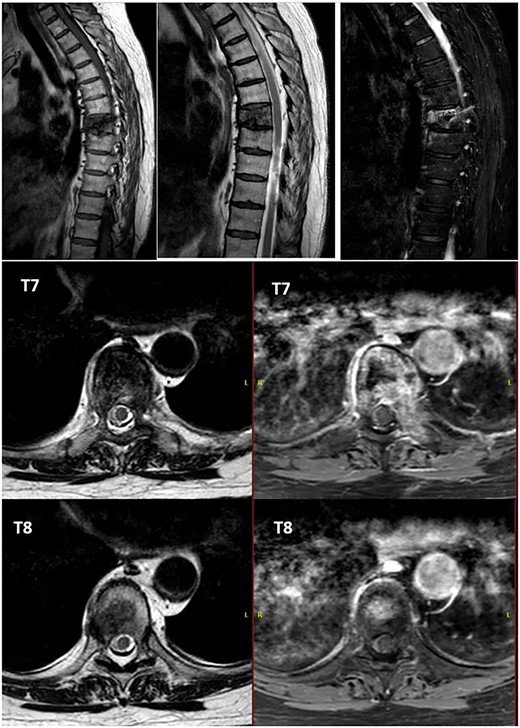

Alteration in the morphology and signal of the T7 vertebral body that presents a fracture with 30% loss of height and dorsal protrusion of posterior wall, with a left and epidural soft tissue component, the signal change extends to the left pedicle and part of the posterior arch. The right lateral margin of T8 vertebral body presents a hypointense signal on T1 and markedly hyperintense on STIR that indicates the presence of osseous edema. These findings suggest T7 pathological fracture and bone edema in the left T8 pedicle.

After PET scan, metastatic disease was discarded. Complete spine magnetic resonance and thoraco-abdominopelvic CT indicated the location on T7 vertebral body, with both end plates broken and causing a leakage to intervertebral disks. Moreover, an intensity change in the left pedicle of T8 was found, which could not be discarded as tumoral (Figs 2 and 3). Surgical resection been the only possible treatment, the patient was appointed to undergo total en bloc vertebrectomy of T7 and T8 and partial of caudal T6, following the technique described by Tomita et al. [1]